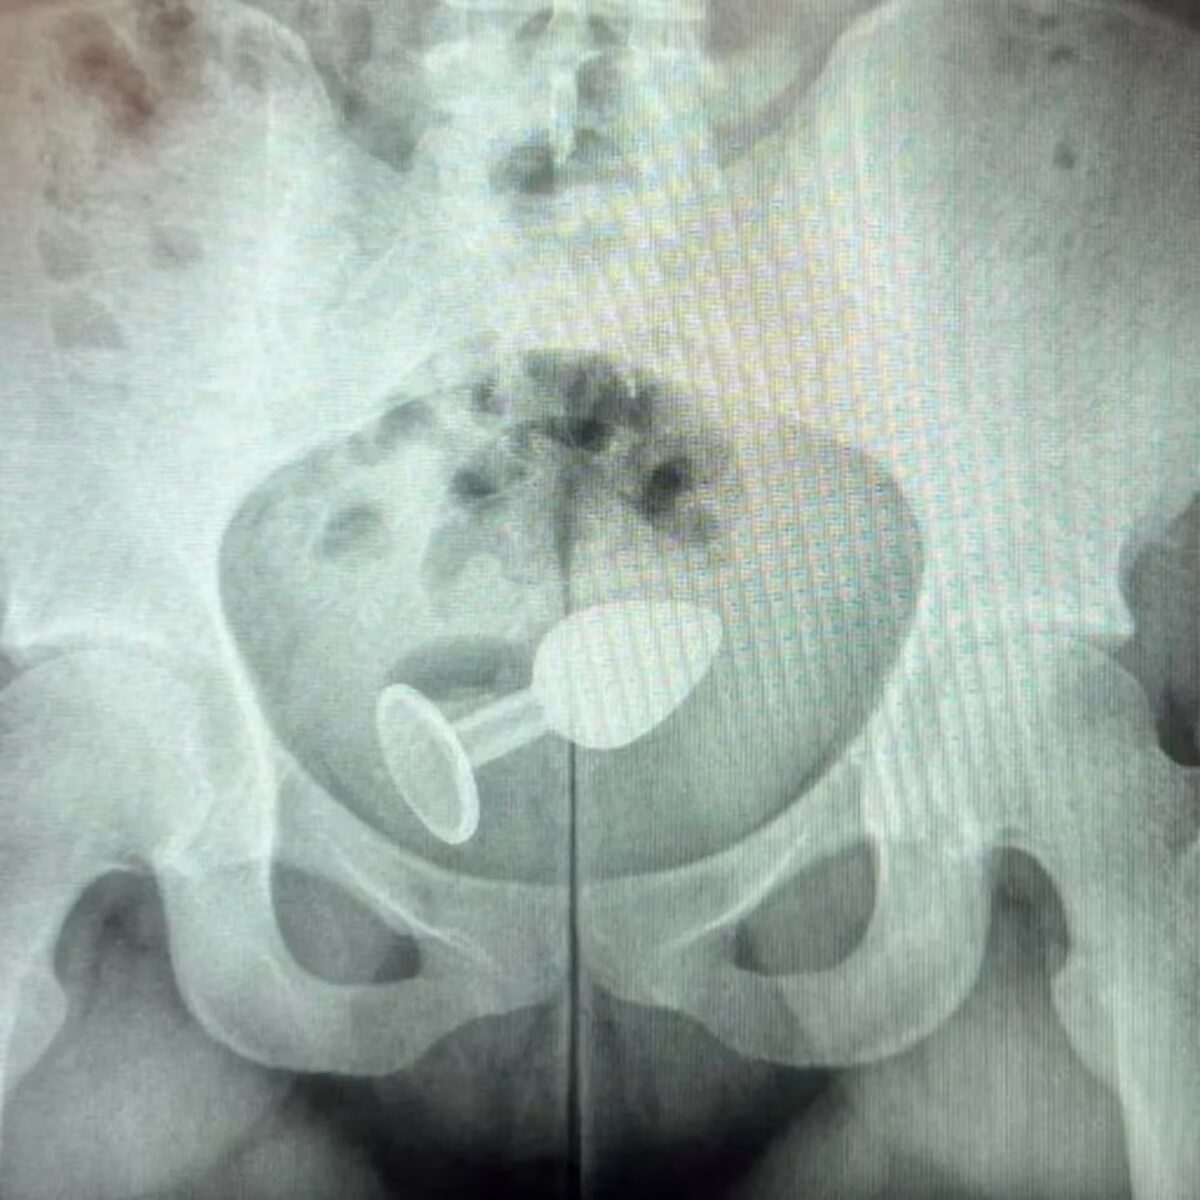

El doctor Daniel Brosco, cirujano coloproctólogo, al realizar una radiografía a la mujer observó el juguete sexual dentro del cuerpo.

La mujer se había colocado un “plug anal”, pero en medio del acto sexual el juguete le provocó una grave herida, por lo que se trasladó de inmediato al hospital.

Ante ello, la paciente tuvo que ser internada para extraer el juguete sexual, aunque no requirió cirugía.